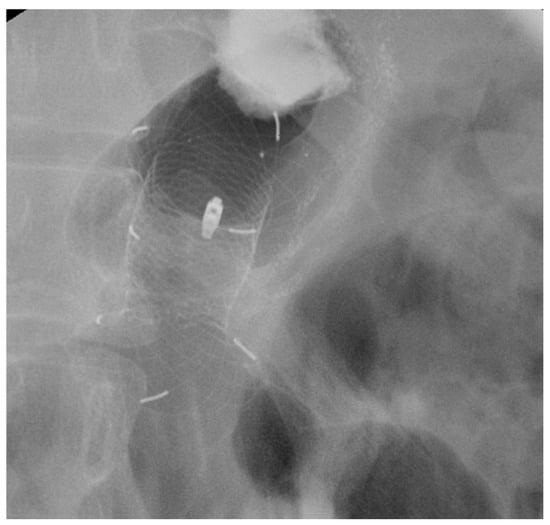

4.1.2. LAMS

Indication and Mechanism of Action

- Direct technique: puncture of the jejunal loop with a 19G needle and contrast injection to confirm position [126].

- Device-assisted EUS-GE: balloon or enteroscope passed across the stenosis to aid EUS visualization and targeting [127].

- Wireless Endoscopic Simplified Technique (WEST): described by Bronswijk et al. in 2020 and currently the most widely used technique [128], this approach involves jejunal distension via a nasoenteric tube with saline and dye, followed by “free-hand” single-step LAMS deployment under EUS guidance [128].

Efficacy and Adverse Events